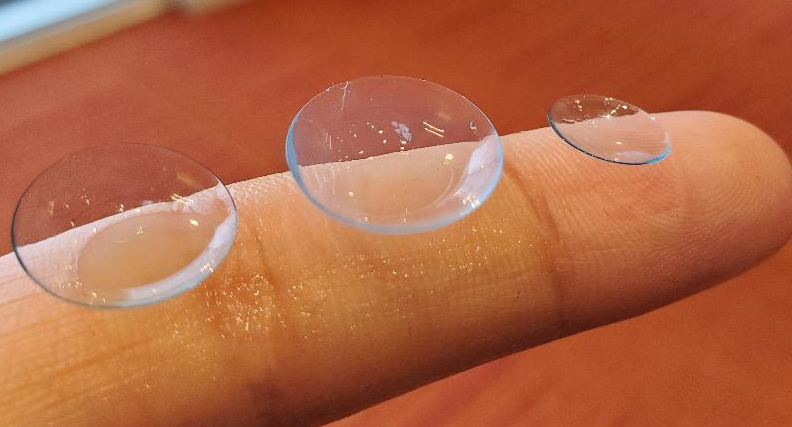

Scleral lenses are large diameter gas-permeable contact lens devices.

Standard Scleral Lenses

For the straightforward case with no need for extra customizations.

Custom Scleral Lenses

When customizations are needed or when conventionals fall short. Includes scan-based, freeform, and EyeFitPro (impression molding). 40,000 data points are collected to create a custom fit lens.

Ultra Custom Scleral Lenses

For the ultimate precise fit and full customization options utilizing impression molding (EyePrintPro). 80,000 points of data are collected to create a truly unique scleral lens.